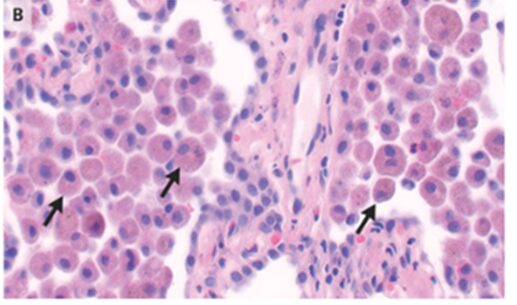

組織病理所見はHE染色で間質の線維化と肺胞内にマクロファージが大量に充填されている像が確認された。

以上から喫煙関連特発性間質性肺炎(剥離性間質性肺炎、DIP:desquamative interstitial pneumonia)と診断された。